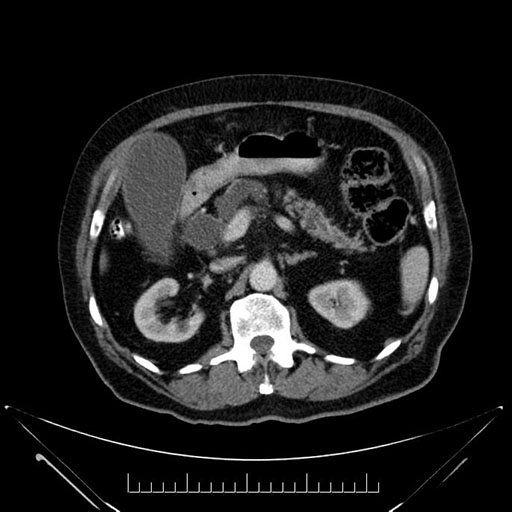

Axial - stented